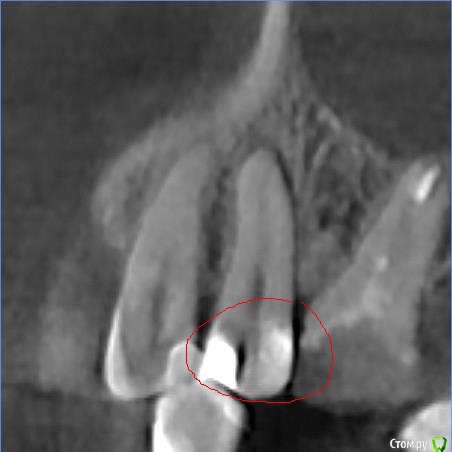

Faramir Опубликовано 30 апреля, 2019 Поделиться Опубликовано 30 апреля, 2019 (изменено) Посетил клинику в которой врач (причем главный) диагностировал кариес между 1.5 со стороны 1.4. На зубе уже была другая пломба со стороны 1.6. Через несколько месяцев я сделал КТ для консультаций по имплантации и рассматривая этот зуб заметил что под пломбой видна не маленькая полость. Обратился в клинику к врачу, после чего мне был вынесен вердикт что это "рог пульпы" и вроде как все нормально. Вопрос может ли быть рог пульпы в 1.5 зубе так высоко и прилегать непосредственно к пломбе черным пятном? Или это банальная ошибка врача который не достаточно утрамбовал материал или материал был не достаточно текуч для заполнения всей просверленной полости? Зуб слегка поднывает иногда. Во что может вылиться если зуб оставить как есть или его нужно обязательно переделать? Фото с КТ прилагаю. Изменено 30 апреля, 2019 пользователем Faramir Ссылка на комментарий

St. Опубликовано 30 апреля, 2019 Поделиться Опубликовано 30 апреля, 2019 Да, все нормально.Впринципе на любой кт присутствуют артефакты и она не предназначена для диагностики кариеса под пломбами 2 Ссылка на комментарий

DmitrySH Опубликовано 1 мая, 2019 Поделиться Опубликовано 1 мая, 2019 (изменено) КТ насколько я знаю является самым совершенным средством диагностики и контроля на сегодня. Но не для кариса под пломбами. т.к. любой пломбировочный материал дает искажение.Это не значит, что у вас там его нет или он есть. Как уже написали выше: очный осмотр и рентген будут более информативны Изменено 1 мая, 2019 пользователем DmitrySH Ссылка на комментарий